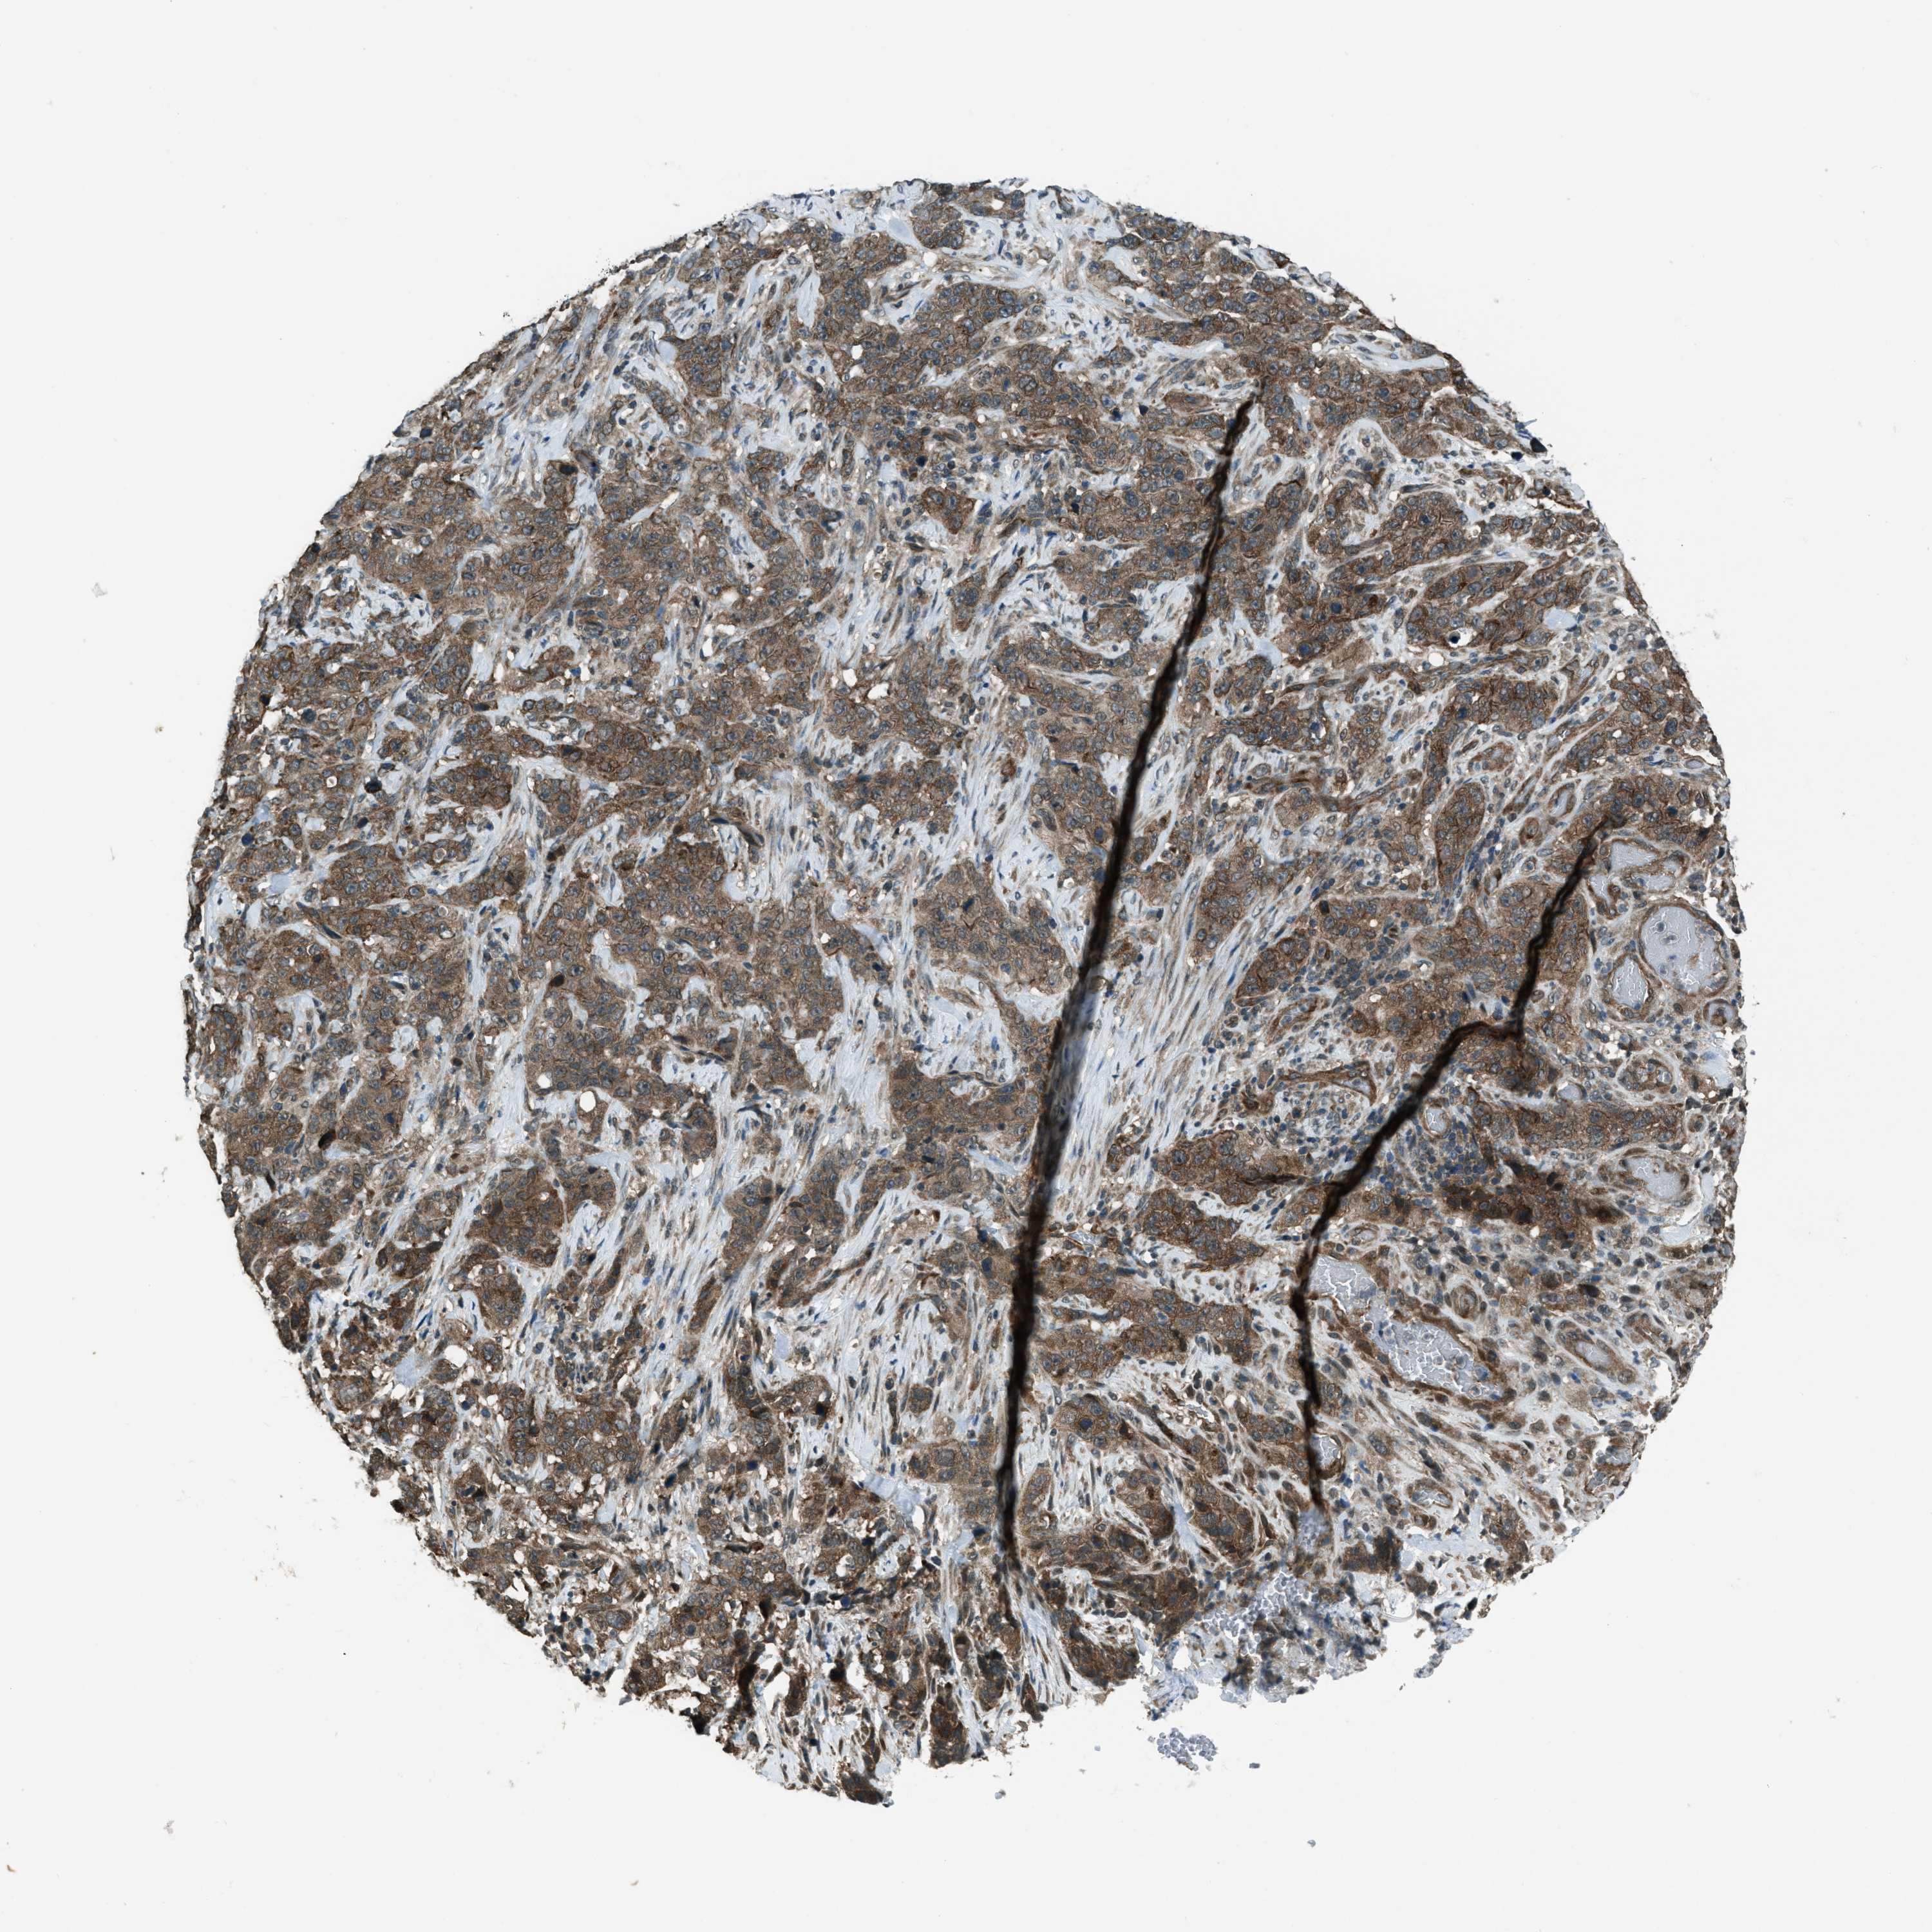

STOMACH CANCER - Protein expressioni

A mouse-over function shows sample information and annotation data. Click on an image to view it in a full screen mode. Samples can be filtered based on level of antibody staining by selecting one or several of the following categories: high, medium, low and not detected. The assay and annotation is described here.

Note that samples used for immunohistochemistry by the Human Protein Atlas do not correspond to samples in the TCGA dataset.

Antibody stainingi

Antibody staining in the annotated cell types in the current human tissue is reported as not detected, low, medium, or high, based on conventional immunohistochemistry profiling in selected tissues. This score is based on the combination of the staining intensity and fraction of stained cells.

Each image is clickable and will lead to virtual microscopy that enables deeper exploration of all samples and also displays staining intensity scores, fraction scores and subcellular localization as well as patient and tissue information for each sample.

Antibody CAB018615

Staining

High

Medium

Low

Not detected

Intensity

Strong

Moderate

Weak

Negative

Quantity

>75%

75%-25%

<25%

None

Location

Nuclear

Cytoplasmic/membranous

Cytoplasmic/membranous,nuclear

Adenocarcinoma, NOS

Adenocarcinoma, High grade